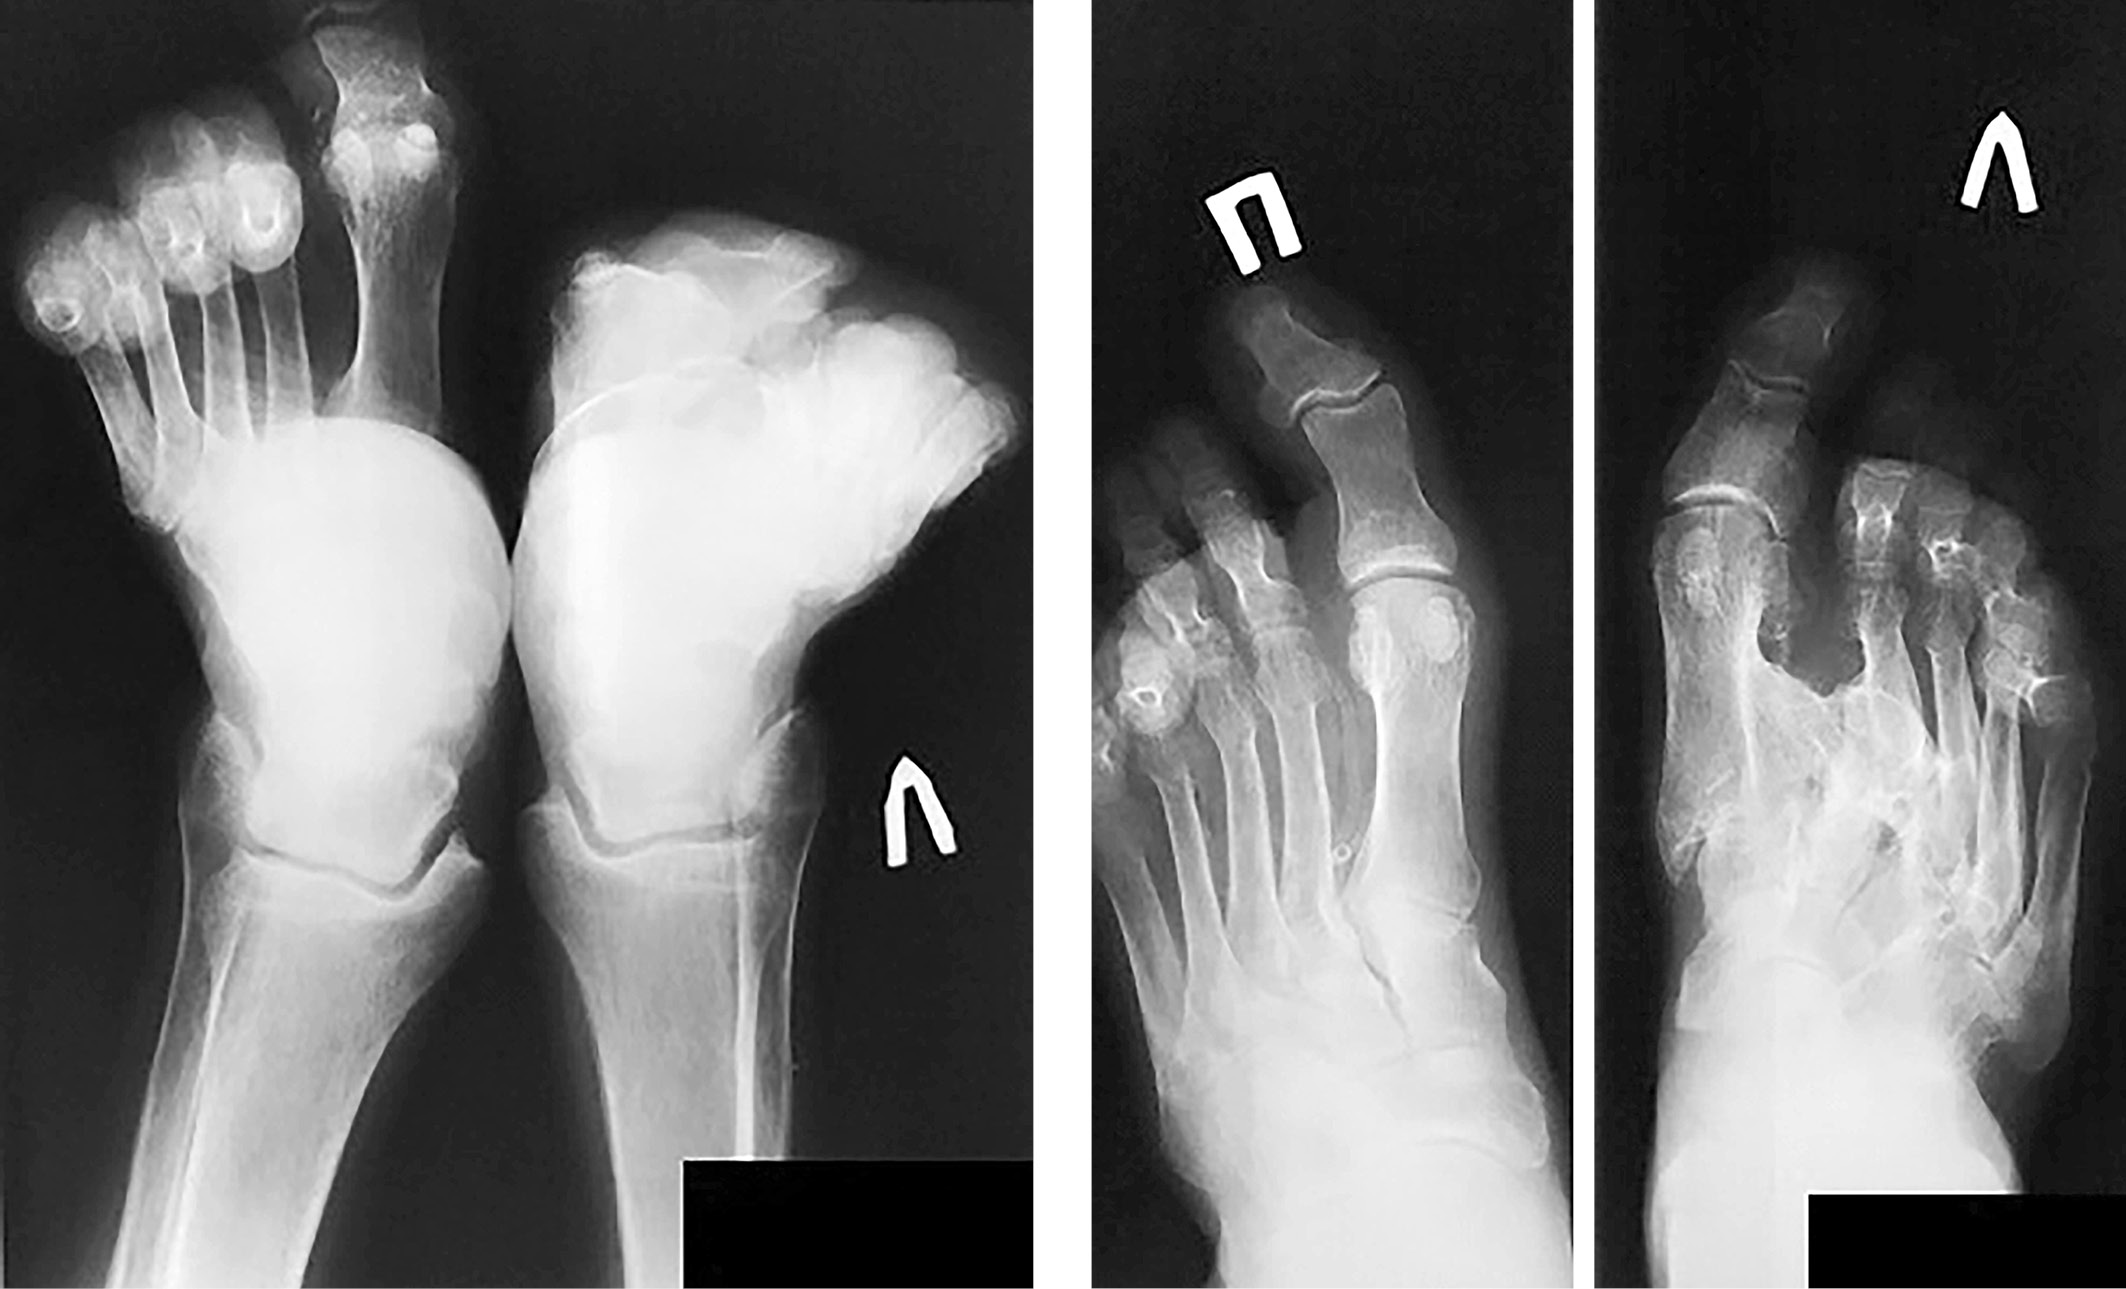

В 2016 г. зафиксирована грубая артропатическая перестройка структуры костей предплюсны и межплюсневых сочленений слева со вторичными подвывихами в них, грубый вторичный правосторонний артрозоартрит коленного сустава на фоне посттравматической чашеобразной деформации медиальных мыщелков правой бедренной и большеберцовой костей, подвывих справа (рис. 4).

Рис. 4. Рентгенограмма обеих стоп, 2016 г.

С 2004 г. на рентгенограммах голеностопных суставов – выраженный грубый остеопороз, в области латеральных лодыжек – зоны Лоозера. Имеется дугообразная деформация плюсневых костей. Головка левой плюсневой кости утолщена, имеет остеопоретически-остеосклеротическую метаплазию костных балок с периостальными и параоссальными наслоениями. В мягких тканях IV стадия кальцификации (рис. 3).

Рис. 3. Рентгенограммы голеностопных суставов, 2004 г.